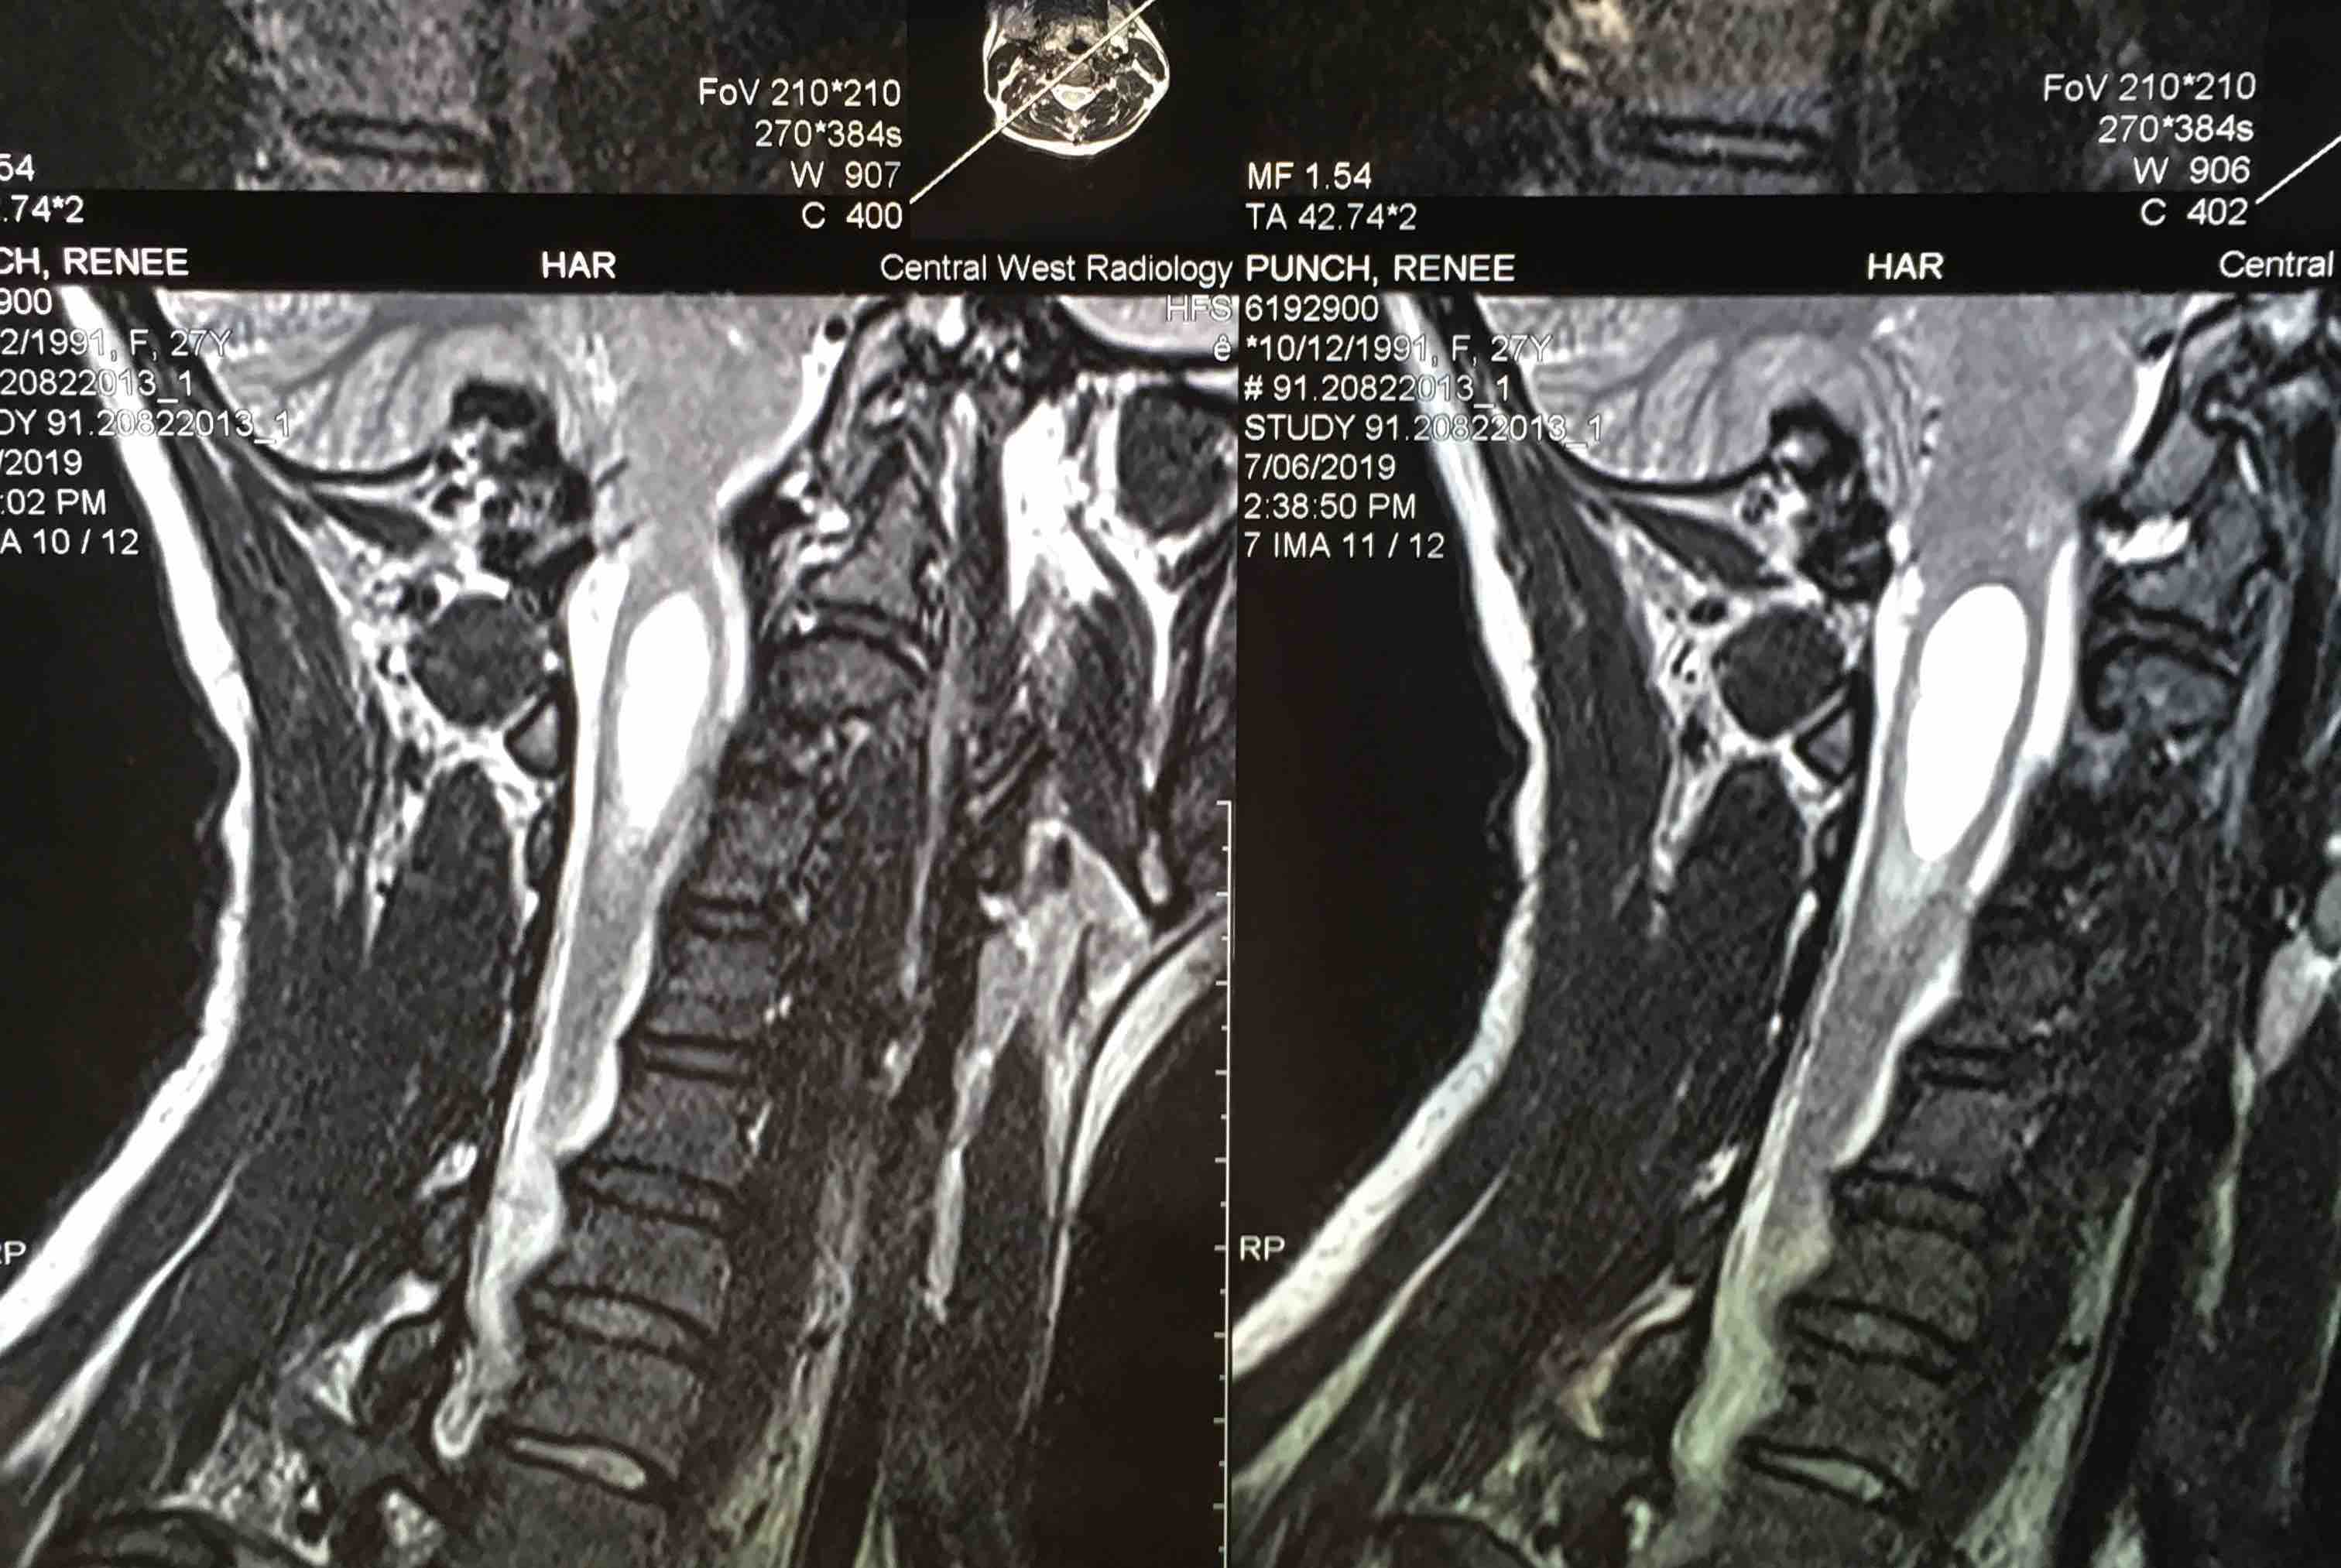

From www.reddit.com

MRI images for possible Trigeminal Neuralgia post orbital Is Decompression Surgery Brain Surgery The main operation for chiari malformation is called decompression surgery. A procedure to relieve symptoms and restore normal cerebrospinal fluid (csf) flow. The most common type of surgery for cm is called posterior fossa decompression. This procedure creates additional space around the lower part of the brain, helping reduce pressure and. Chiari decompression surgery is performed to help create more. Is Decompression Surgery Brain Surgery.